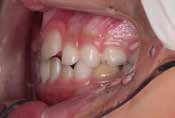

下の奥歯が内側に傾いて、舌の位置が悪く、鼻がつまって口呼吸の状態でした。扁桃腺がよく腫れ、風邪をひきやすく、いびきもあるようでした。

治療を終えて

装置で上あごを拡大し、下の歯の位置を整え、前歯の並びを整えました。お口のトレーニングの効果で鼻詰まりと、いびきも改善。たった1年でこの変化が見られました。もちろん歯は1本も抜いていません。

主訴・治療内容 他院にて「抜歯した上で、ワイヤーを付け、5年かけて治療する」と言われ、他の方法はないのかとネットで調べたところ、当院を知り無料相談に来院されました。